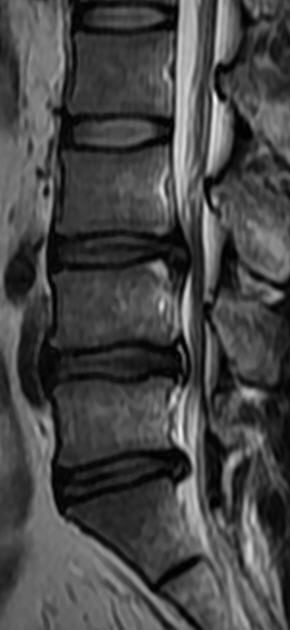

MRI

可提供腰椎管的矢状面、冠状面和轴位横断面上的影像。椎管狭窄以T2加权像显示较好,脑脊液为高信号,产生所谓“脊髓造影”的效果,而骨质增生,骨赘、间盘均为低信号,能清晰地显示椎管狭窄,以及对脊髓的压迫情况。但对肥大的黄韧带、骨质增生等的判断则不如较高清晰度CT扫描。

腰椎正常MRI解剖。

腰椎管狭窄MRI表现。